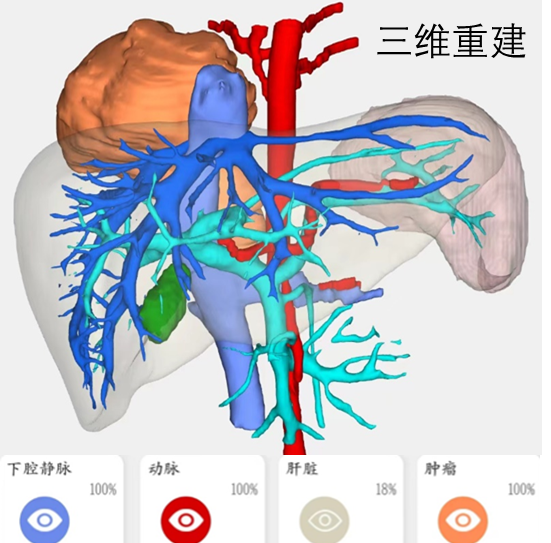

渭南某地10岁小姑娘因为间断性的腹痛到医院检查,意外发现腹腔内有一直径超过10cm巨大肿瘤。慕名来到我院小儿外科就诊。常规的超声检、磁共振和CT检查,都提示腹膜后有一个巨大肿瘤,而且这个肿瘤位置非常特殊,它长在肝脏、下腔静脉和腹主动脉等重要脏器和血管的后方,膈肌的下方,如果按照常规的手术思路,经腹手术,暴露困难,视野不佳,手术的难度和风险极大,而且只能是开放手术,创伤也会大大增加。

怎么样能够降低手术风险,也能够达到家属期望的微创治疗?经过多次讨论,鉴于肿瘤巨大及特殊位置,李鹏教授团队突破常规思维,提出经胸腔镜下切除腹膜后肿瘤的方案,利用胸腔空间大,切开膈肌后,暴露充分,手术的风险和难度反而大大降低,而且李鹏教授团队有丰富的胸腔镜操作的经验和技术,经过反复研究影像学资料和讨论,最终制定了胸腔镜下腹膜后肿瘤切除的方案及备选方案。

术前准备就绪,2023年9月6日在麻醉科李有才教授团队、及手术室护理团队的配合下,手术顺利开始,胸腔镜进入右侧胸腔后清楚可见突入胸腔内的巨大包块,切开肿瘤表面的膈肌,可以见到肿瘤与膈肌尚有分界,一切正如手术前所设想,每一次解剖与游离在李鹏教授精细的操作下顺利进行,大约2个小时肿瘤成功切除、膈肌修复完整,经过小小切口放入标本带将切除的肿瘤全部取出。胸腔镜手术切除巨大腹膜后肿瘤成功进行,达到了预期设想的安全、可靠、微创的效果。